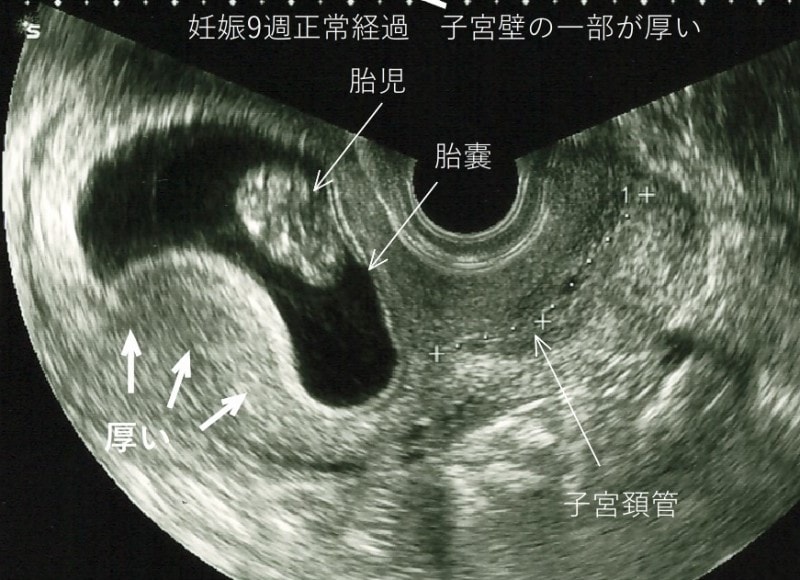

■子宮壁の伸展子宮壁は受精卵が着床した付近から柔らかく薄くなりますが、妊娠初期は硬く厚いところもあります。 ゴム風船を膨らます時、ゴムの厚さにムラがある間は膨らみにくく、ムラなく伸び始めると、急に風船は膨らみやすくなります。

子宮も妊娠4ヶ月までは、子宮壁に厚い部位があり、痛みやチクチク感の原因になります。妊娠5ヶ月には、ほぼ全体の筋肉が伸びて症状は軽減します。昔から、妊娠5ヶ月からを安定期とするのは、胎盤の完成と子宮壁の伸展が理由です。子宮筋腫があると子宮壁は伸びにくく、痛みを感じやすくなります。